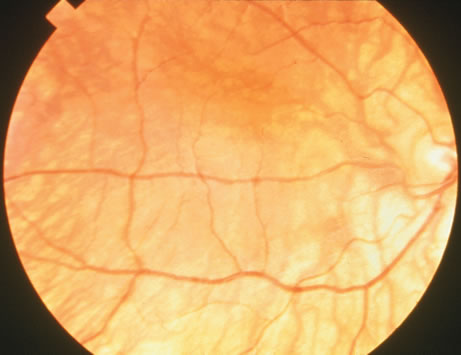

Clinically, funduscopic changes are initially apparent in the mid-peripheral fundus, with progression toward the macula and the far-periphery (Fig. 4A). These changes include RPE stippling and atrophy, with focal loss of choriocapillaris and prominence of the underlying choroidal vessels surrounding the optic disc (Fig. 4B). Early in the disease process, areas of skip lesions are clearly evident on fluorescein angiography. Additionally, scattered intraretinal pigment clumps at the equator and midperiphery may be noted. At this early stage, abnormal light and dark adaptation can be detected, and the electroretinogram (ERG) reveals reduced rod responses. Patches of chorioretinal degeneration occur near the equator and eventually advance, with loss of the normal choroidal pattern and diffuse RPE and choroidal atrophy except in the macular region. However, no intraretinal pigment migration occurs, as in retinitis pigmentosa.21 The macular area is the last to be affected and is usually the only area of normal tissue left in the late stages of the disease. In the final stages of choroideremia, the scotopic ERG is unrecordable.16,18

Fig. 4. A. Choroideremia in a male patient. There is loss of the retinal pigment epithelium and prominence of the choroidal pattern in the periphery. There is sparing of the macular region. B. Portions of the retinal pigment epithelium under the fovea still are intact in the late stages of choroideremia. (A and B courtesy of J. M. D. Gass, M.D.)